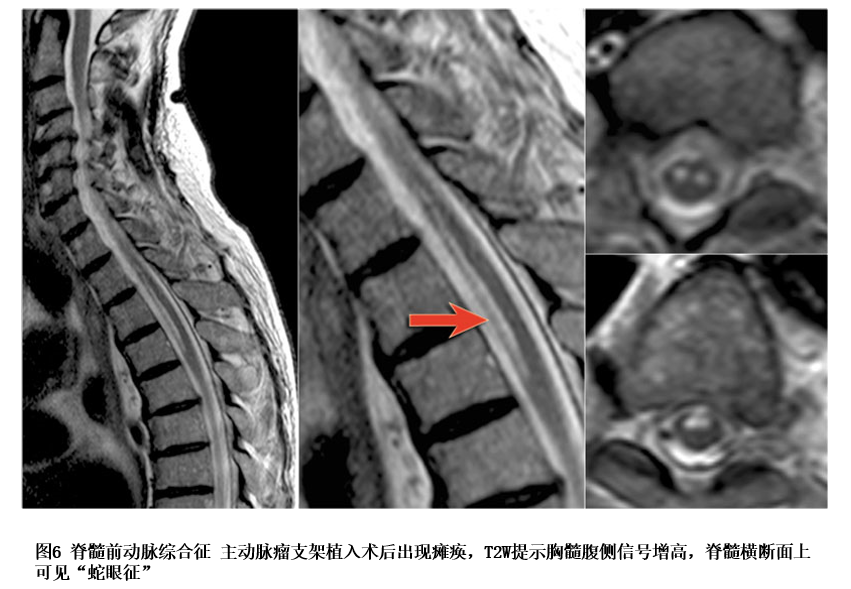

mri特点是较长节段的双侧前角灰质,皮质脊髓束和脊髓丘脑束损伤,通常

图片尺寸708x675